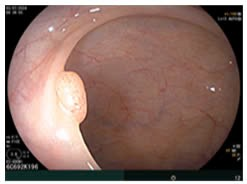

- Nội soi đại tràng:

Hình 6: Hình ảnh nội soi: đại tràng sigma có polyp kích thước khoảng 0.4cm